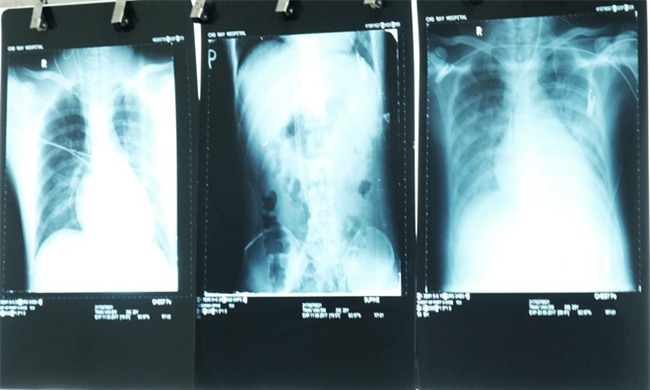

Ảnh chụp X-quang khu vực tim của bệnh nhân.

"Với

tình trạng này, biện pháp duy nhất là tiến hành đặt máy tạo nhịp ECMO

cho bệnh nhân. Sau khi đặt máy, cơ tim bệnh nhân có cải thiện nhưng vì

đã quá nặng từ trước nên thận đã suy, phổi phù, tim chỉ còn co bóp

khoảng 25%" – BS Linh chia sẻ.

4 ngày sau khi chạy ECMO, tim bệnh nhân có khá hơn nhưng thận vẫn chưa hồi phục. Cách hai ngày, bệnh nhân phải lọc nước tiểu 1 lần và được lọc máu liên tục.